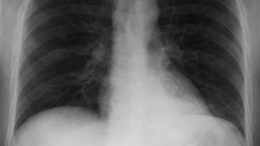

Έξαρση των ιώσεων αλλά και της πνευμονίας παρατηρείται τις τελευταίες…